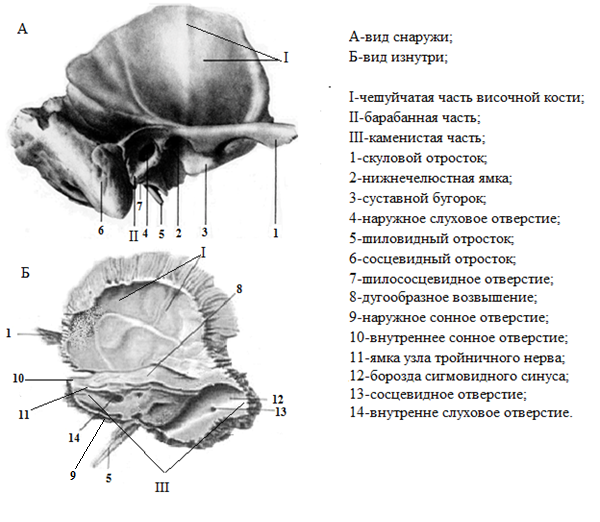

Анатомические изображения срединной сагиттальной линии черепа